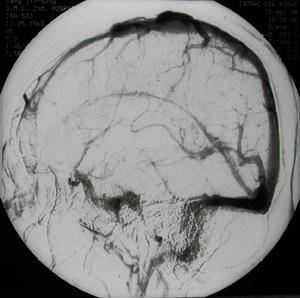

3、腦血管造影。

Saito等(1977年)將Pool&Pott對CVS的分類法加以改良分為三型:1型:廣泛而瀰漫的腦血管變細,範圍涉及頸內動脈、大腦中動脈與大腦前動脈的近段,血管呈線狀纖細;2型:廣泛性或多支腦動脈細狹,呈節段性的狹窄;3型:動脈細狹只限於動脈瘤的鄰近的動脈分支。

Auer(1984年)將CVS分為三級:1級:局部血管痙攣範圍不到50%;2級:局部血管痙攣,範圍超過50%;3級:瀰漫而廣泛的痙攣。

CVS分為兩期,SAH後1~3天為急性期,隨後是慢性痙攣期,可持續約10~14天后才逐漸消退。腦血管急性痙攣期死亡率高,以顱內壓增高、腦血流量降低和腦灌注壓降低為特徵。SAH後早期發生的腦血管收縮在動物模型上十分明顯,在人類較少發生。但是顱內壓增高、腦血流量降低和腦灌注壓降低提示微循環已受影響。一些研究者認為該期對藥物治療較為敏感。而慢性CVS是造成神經功能損害和致死的主要原因,並且對藥物治療反應較差。現在還不清楚急性CVS是否加速或加重遲發的CVS。病理學研究表明,發生痙攣的血管內皮細胞腫脹,部分脫落,內膜增生,中層平滑肌細胞變性、壞死,外膜有大量的粒細胞和巨噬細胞浸潤等炎性改變是慢性CVS的主要特點。